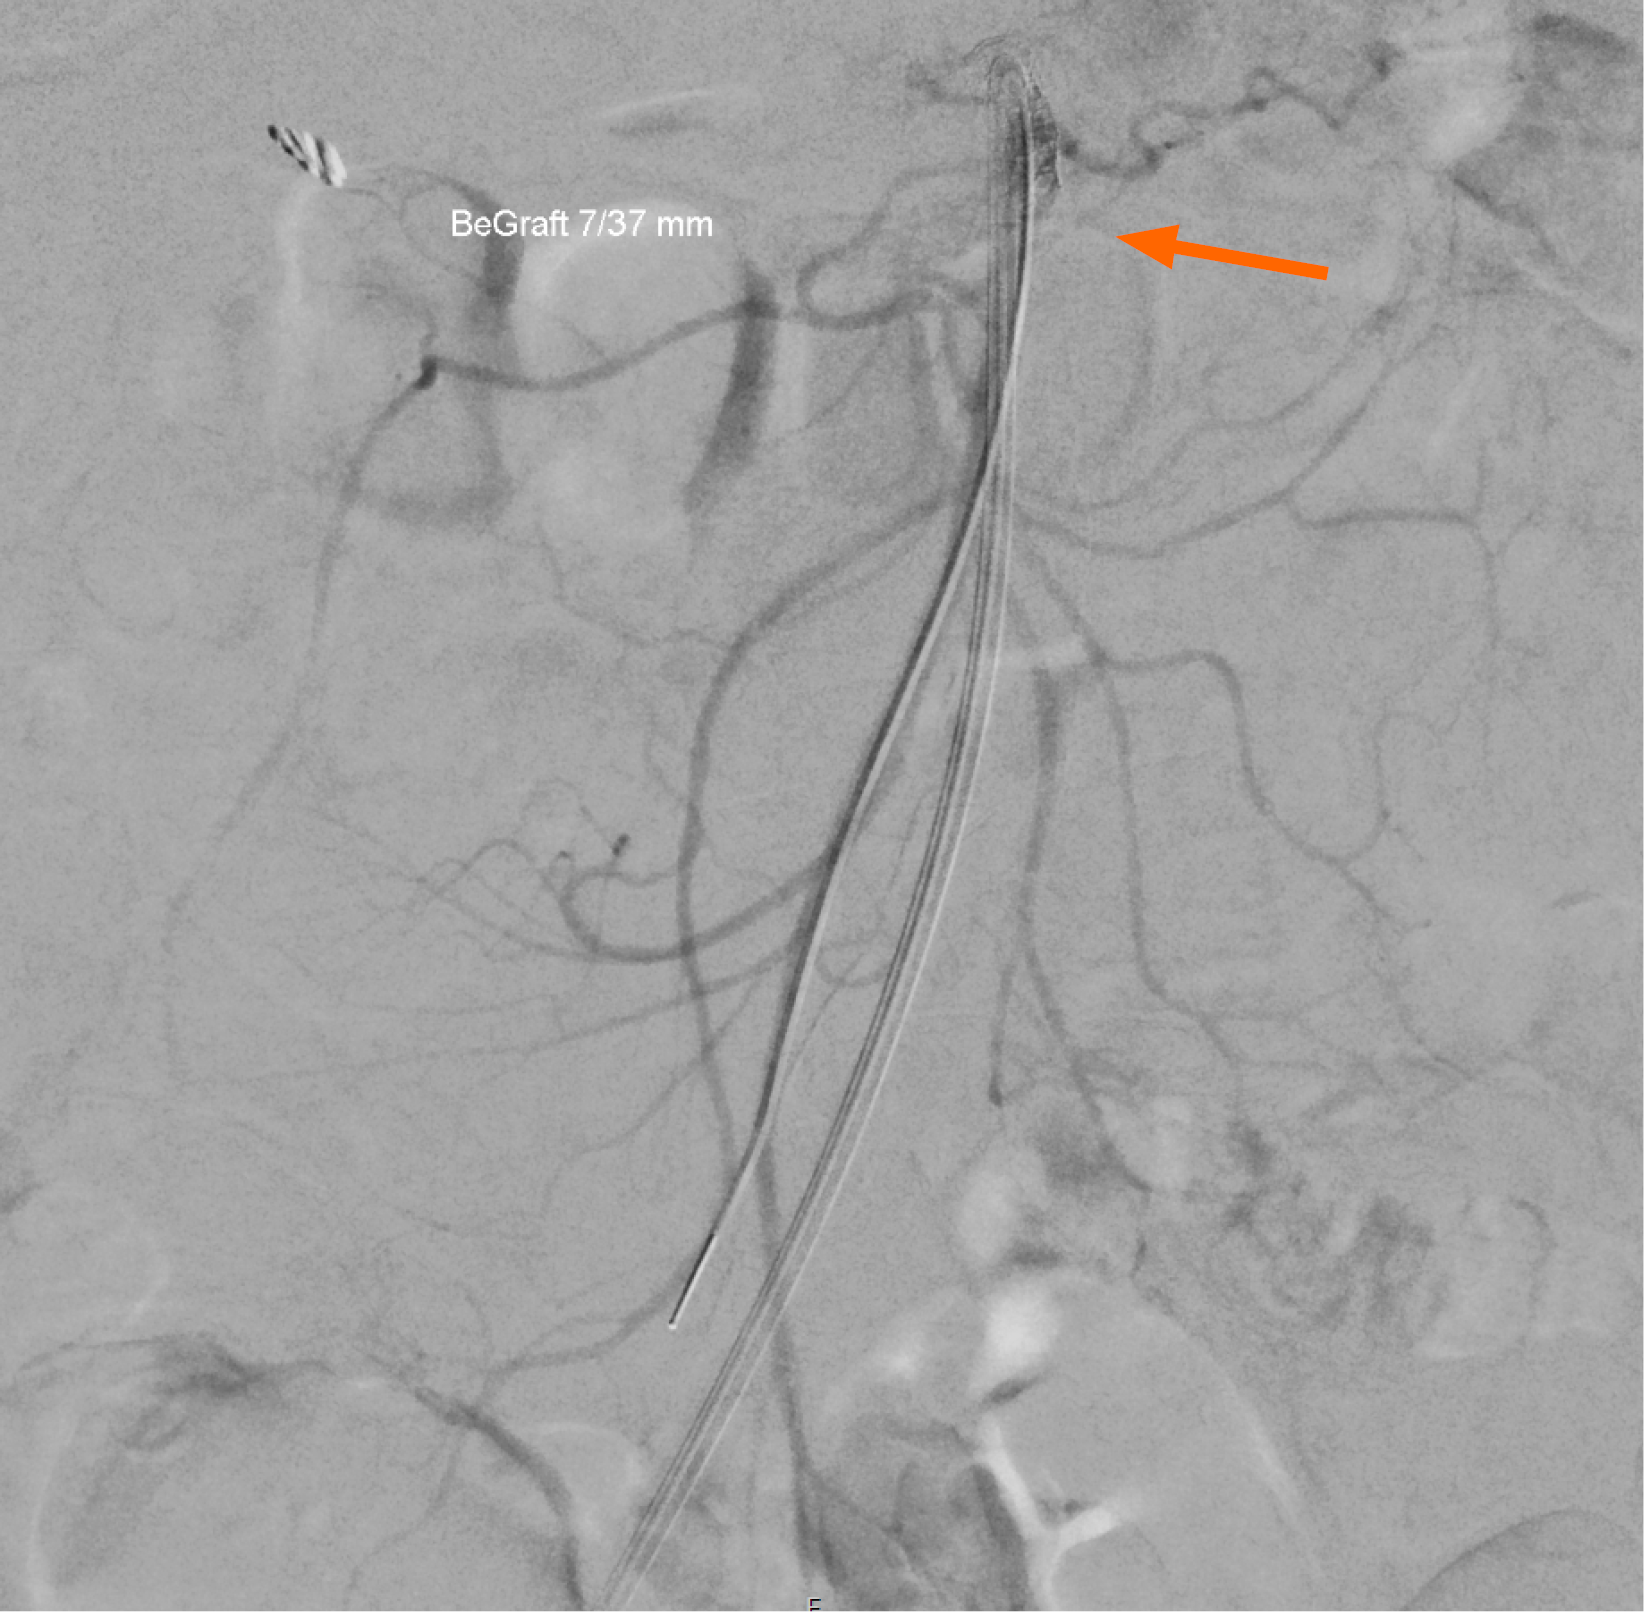

Case 2: The abdominal CT performed for investigation of the patient´s symptoms several months prior was re-reviewed by the gastroenterology registrar, revealing marked calcification at the SMA and celiac origins, not mentioned in the radiology report (Figure 2A and B). CT angiography confirmed high-grade stenosis of the SMA (Figure 2C and D). Figure 2A and B (CT abdomen protocol) show the presence of significant calcification at both the celiac trunk and SMA (Figure 2A, sagittal reconstruction), with extensive calcification at the SMA ostium when viewed in axial view. The SMA show extensive calcification along the entirety of its length especially in sagittal view. Figure 2C and D (CT angiography protocol) show extensive calcifications at both the celiac trunk and SMA (Figure 2C, sagittal reconstruction). Panel D shows extensive calcification at the SMA ostium when viewed in axial view.

Both patients were referred to the vascular surgery service for further management and endovascular stenting. The patients underwent successful percutaneous angioplasty with stenting, demonstrated as completion angiograms in Figure 3 (Case 1) and Figure 4 (Case 2). Both figures show patent SMA with good contrast filling distally, indicating restoration of adequate mesenteric blood flow. Case 1 had regained approximately 5 kg 11 months post-endovascular intervention with resolution of post-prandial pain. Case 2 had regained approximately 8 kg 6 months post endovascular intervention with resolution of post-prandial pain.